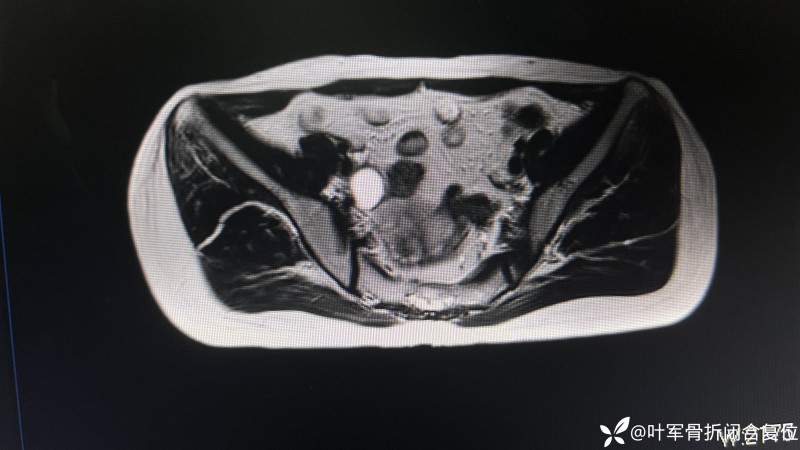

影像学检查的结果更是为诊断提供了重要依据。腰椎MRI虽然提示了腰4/5椎间盘损伤,但并不能解释腹股沟区的疼痛。于是,他们建议进行骨盆磁共振检查(MRI),这一查,果然有了重大发现——右侧髂腰肌下方存在液性区,而这个液性区,恰巧位于股神经及腰丛区域。结合患者的症状、查体结果以及影像学发现,真相逐渐浮出水面:患者的长期腹股沟疼痛和偶发的大腿无力,很可能与股神经在髂窝区域的受压或病变有关。